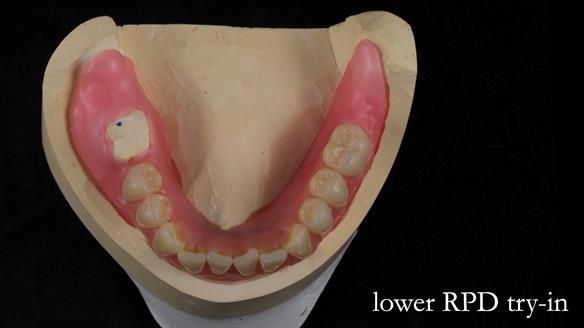

- Mk 2 lower metal-based RPD

The original plan was to finish the lower as a conventional metal-based partial denture, as shown in the initial design below.

However, once Rowan and I reviewed the remaining metal crown on tooth 46, we realised it would make an ideal abutment for a gasket denture. By reshaping the lingual surface of the crown, we created an excellent gasket seal.

This approach worked far better than the proposed ring-clasp design - improving retention, comfort, and aesthetics while keeping the design clean and simple.